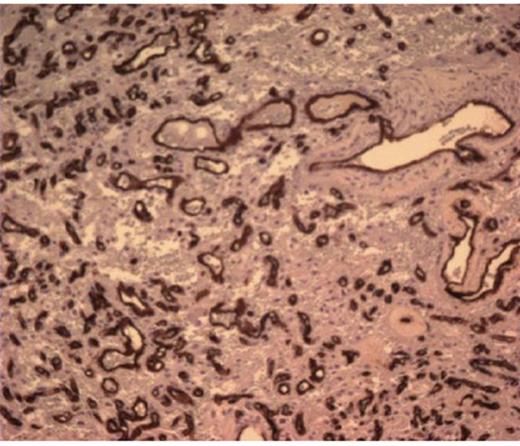

She was taken to the operating the following morning for a bicoronal craniotomy for a gross-total tumor resection with neuronavigation (Fig 2). Pathology was a dural-based WHO Grade 1 supratentorial haemangioblastoma. Microscopic findings demonstrated large vessels and abundant capillary networks, with a cellular proliferation of large stromal cells with clear vacuolated cytoplasm (Fig 3,4,5). There were significant hyperchromatic nuclei and multiple areas of PAS positive pinkish globules (Fig 3,4,5).

10 x Haematoxylin and Eosin stain showing typical microscopic pathology of capillaries and interstitium

CD 34 positive staining of vascular lining consistent with haemangioblastoma

No mitoses were identified. No whorls or psammoma bodies were identified. Immunohistochemical findings showed interstitial tumor cells immunoreactive for NSE, factor X111A, and S100. RCC, EMA, Inhibin, GFAP, CAM 5.2, CD 10, and CD 34 were negative on the interstitial cells. CD 34 was positive on the vascular endothelium (Fig 3,4,5). She was discharged home within six post-operative days. She returned to clinic one week later and had no neurological deficits.

Hyperchromatic nuclei and typical Periodic Acid Schiff + globules at 100x